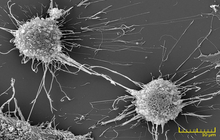

- Examination of cell placement on tissue scaffolds with SEM microscopy